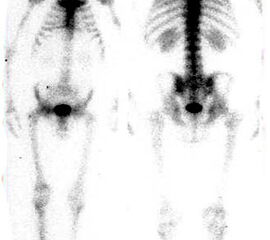

Nur bei Kontraindikationen für ein MRT (z.B. Herzschrittmacher, Metall-Implantate u.a.) sollte alternativ auf die unspezifische Skelettszintigrafie und das CT ausgewichen werden.

Während sich im CT  erst nach Wochen eine Osteopenie darstellen lässt, zeigt sich im Szintigramm bereits im frühen Stadium eine erhöhte Anreicherung des Radionuklids in der betroffenen Region (Abb. 6). Diese ist Folge der verstärkten Vaskularisation und des erhöhten Knochenumsatzes {ref: 15049532, 9462360, 16228105, 15045549}